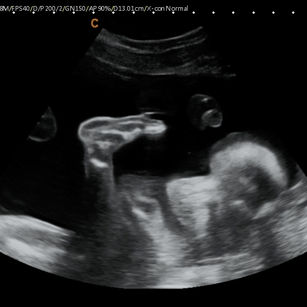

24 Weeks 1 Day Pregnant

Weight: ~1.25 pounds (0.56 kg), the size of an Ear of Corn!

Length: ~12 inches (30.5 cm)

Development Highlights:

Lungs developing more complex airways; surfactant begins forming.

Brain growth accelerates; neurons forming rapidly.

Taste buds fully formed.

Skin is still translucent; vernix caseosa starting to cover more of the body.

Movements: Stronger kicks, flips, and stretches. You may feel patterns of activity.